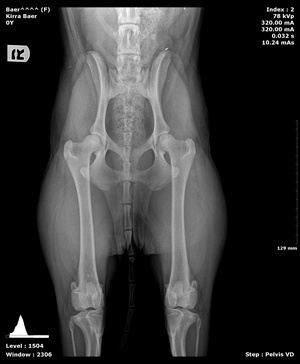

Pennhip X-rays in Williamsfield & Elmwood, IL

Wags and Whiskers is one of the few facilities in the state that offers PennHip diagnostics. PennHipp is a tool used to measure hip laxity. It can detect the presence of osteoarthritis or hip dysplasia in canine companions. Breeders often use this service to determine breeding soundness. It can be performed on patients as young as 16 weeks old.